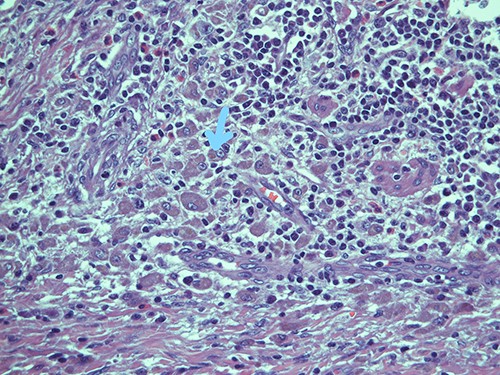

Submucosal cellular population is constituted by round histiocytic elements with a granular dense cytoplasm, containing typical eosinophilic bodies (arrow); haematoxylin and eosin, magnification ×20.